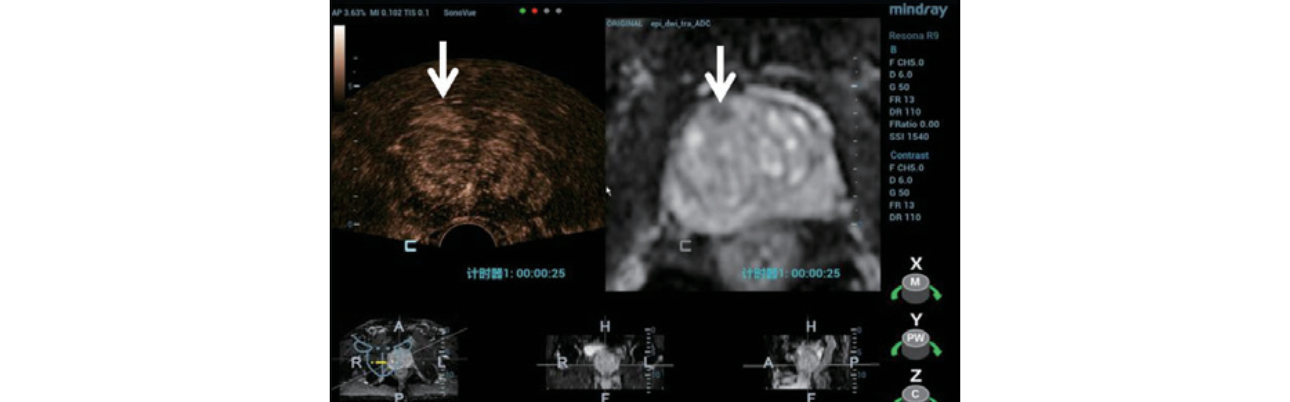

Step 2: 마인드레이의 iFusion 소프트웨어를 사용하여 TRUS/MRI 이미지를 정렬 및 융합(Figure 3) 표적 대상 레이블(Figure 4).

trus-mri-fusion-fig3-pc

형상3. “Plain-to-Plain” 융합을 위한 작은 전립선 낭종 선택.

trus-mri-fusion-fig4-pc

형상4. MRI 영상에 병변이 표시되고, 실시간 초음파 영상에 해당 영역이 표시됨.

Step 3: 병변의 위치를 파악하기 위해 해부학적 참고가 되는 MRI 영상(Figure 5)을 사용하여 조영제 증강 초음파(CEUS)를 실시했습니다.

trus-mri-fusion-fig5-pc

형상5. 조영제 증강 초음파에서는 MRI에서 보인 병변에 해당하는 부위가 반대쪽의 말초 조직 대비 초기 증강을 보여줌.